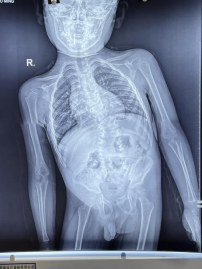

经脊柱侧弯矫形科安晨辉主任查体:患儿头颈部向左倾斜,身体重心向右严重偏离,高低肩明显,骨盆向左偏移后经全脊柱X片显示:中重脊柱侧弯,测量Cobb 角41度,胸4、5、8-12椎体异常,部分为蝴蝶椎,胸9-12、骶椎椎弓根间距明显增宽,侧位胸段稍后凸,腰骶椎轻度反攻,部分肋骨发育异常。

X 片显示

5、全脊柱X片测量 Cobb 角从原有的 41度恢复至26度。